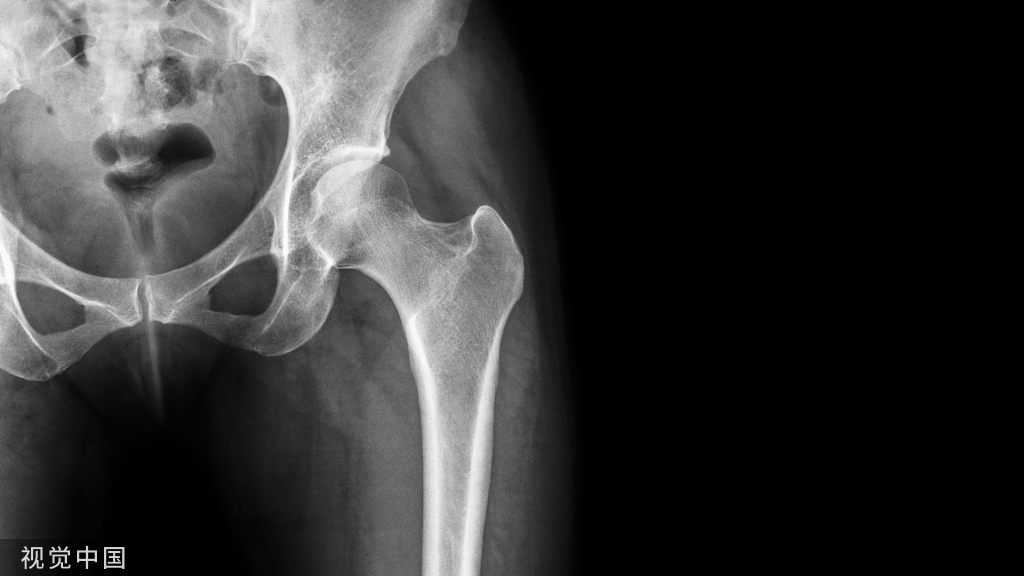

骨质疏松症是一种以骨量低下,骨微结构破坏,导致骨脆性增加,易发生骨折为特征的全身性骨病。

3、脆性骨折

病史和体检是临床诊断的基本依据,确诊依赖于X线检查或骨密度测定。

双能X线吸收法(DXA)是目前公认的骨密度检查。与正常年轻人相比,骨密度下降2.5个标准差诊断OP,即:T值≤-2.5诊断为骨质疏松;-2.5<T值<-1.0为骨量减少;T值≥-1.0为正常。